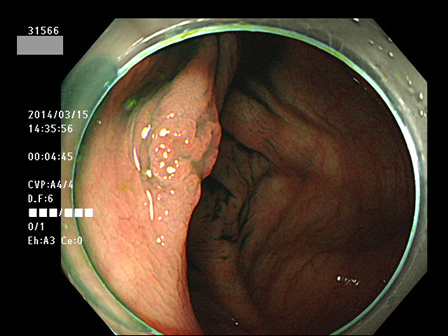

上記100名より抽出した平坦・陥凹型腺腫(=癌化の危険が高いが見落としやすい病変)の内視鏡写真

31532 31533 31534(SSA/Pのみ) 31537 31538 31539 31540 31541 31542 31545 31546 31550 31552 31553 31554 31555 31556 31562(SSA/Pのみ) 31563 31564 31565 31566 31567 31572 31573 31574 31576 31578 31579 31580 31581 31582 31586 31587 31589 31590 31591 31593 31596 31597 31598 31599 ・・・・の65名